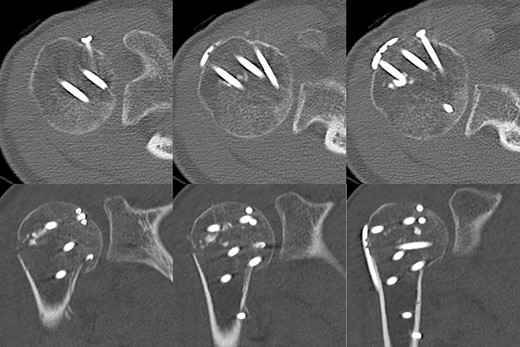

A 39-year-old man was transported via ambulance after being hit by a car. The radiographs revealed a one-part proximal humeral fracture with displacement at the surgical neck (Fig. 1). However, computed tomography (CT) revealed humeral head impression fracture and lesser tuberosity fracture in addition to a surgical neck fracture (Fig. 2). In addition, 3D-CT revealed that the collapse occupied approximately 20% of the articular surface with no glenoid defect (Fig. 3). Therefore, we first performed arthroscopic-assisted reduction and internal fixation of the humeral head impression fracture, followed by open reduction and internal fixation (ORIF) of the proximal humeral fracture.

Original CT scan showing impression fracture and surgical neck fracture.